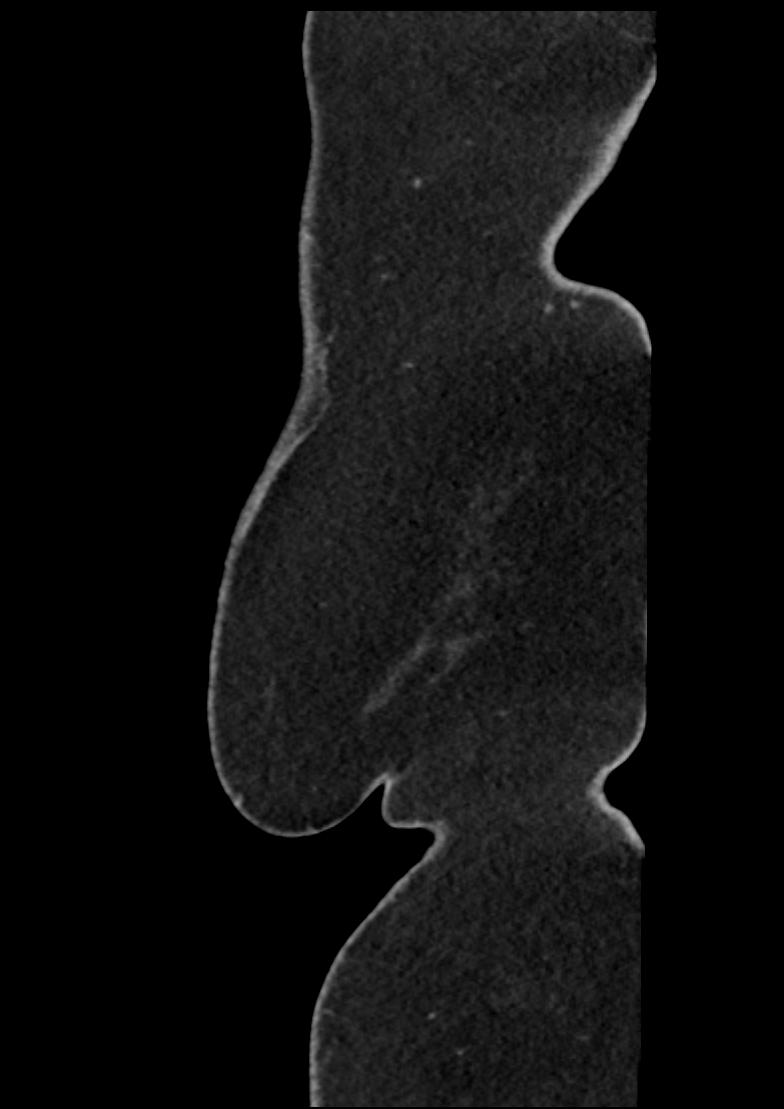

Patient: Padmakumar A. , *1988-04-24, PID: 3000069741773230809

Study Description: CT ABDOMEN

Image Series: Abdomen Sag 3mm [4]